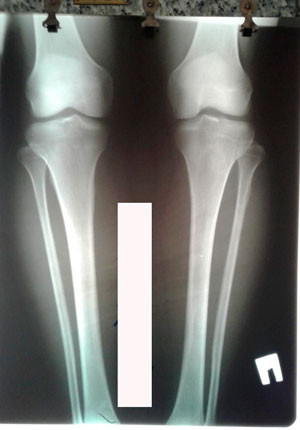

Исходник - 39 лет.

Дата операции - 06.08.2020

image-04-08-20-09-41-2.jpg

image-04-08-20-09-41-5.jpg